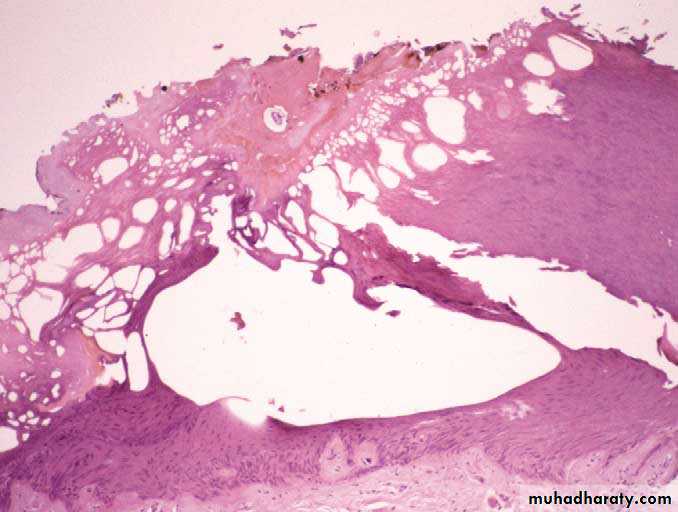

المشاهدات المجهرية عند مدخل التيار الكهربائينلاحظ فراغات نسيجية (فقاعات) استطالة في نوى الخلايا مع حدوث تنخر خثري Coagulative necrosis